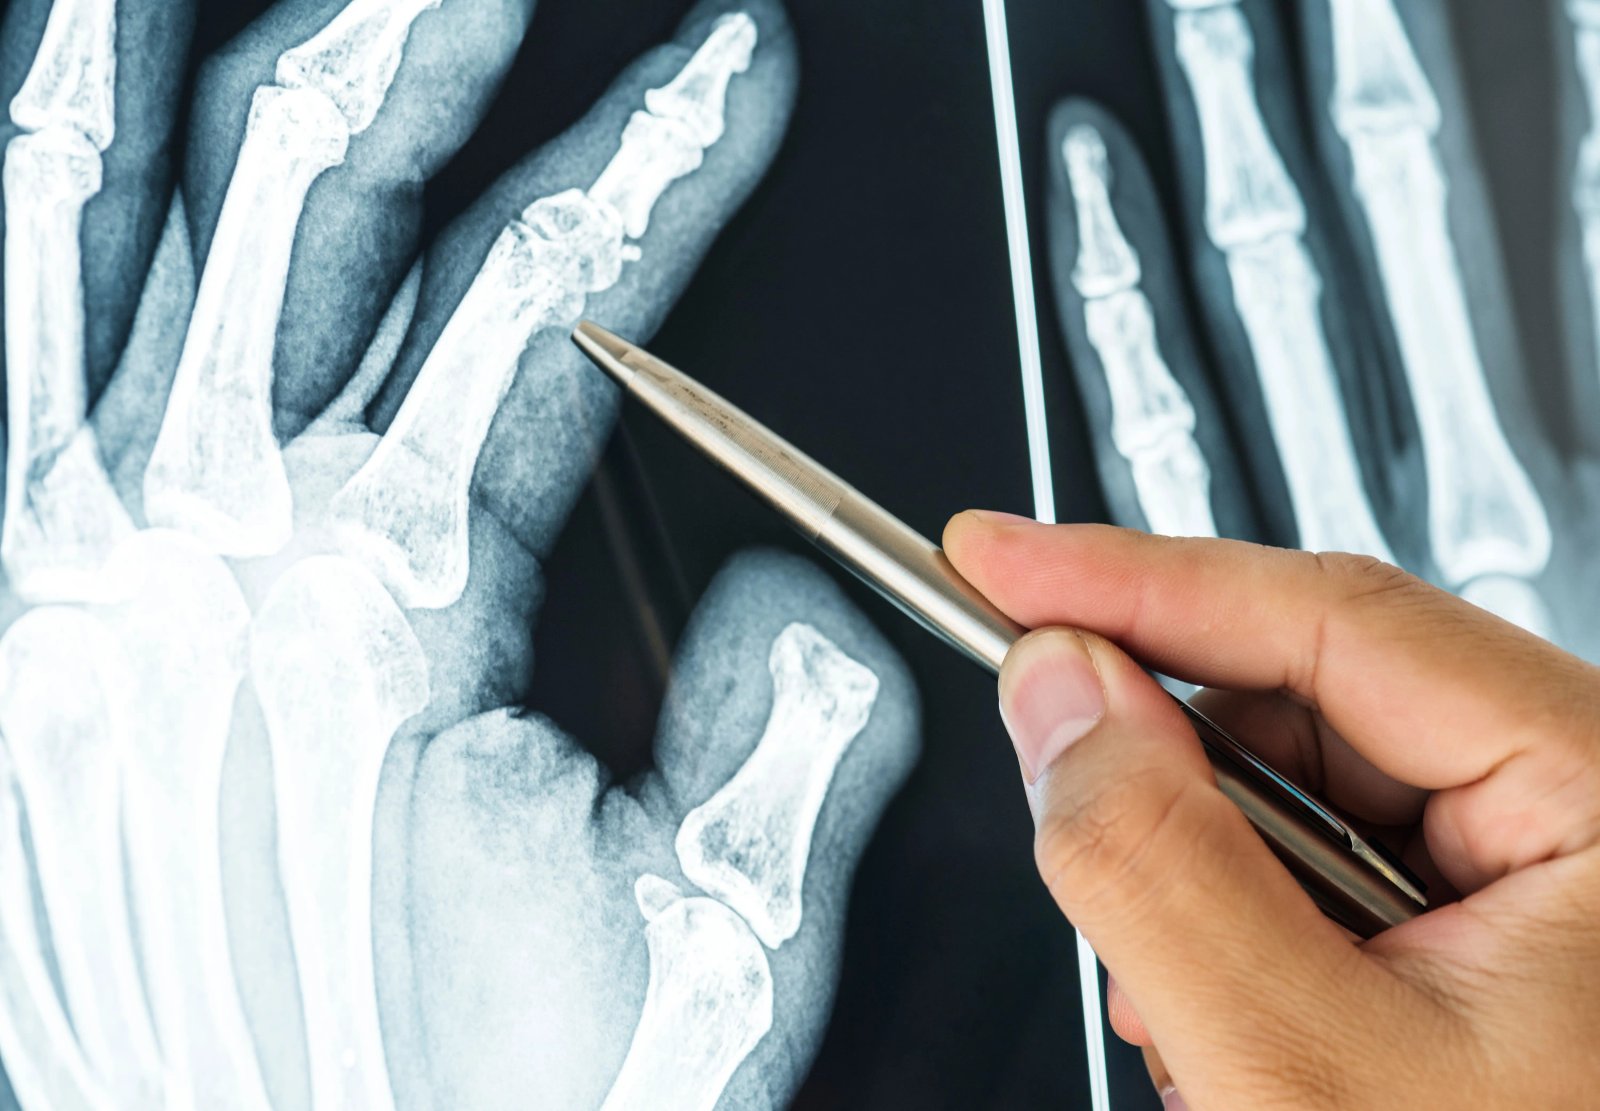

Non Union, Delayed Union, Malunited Fractures

These conditions cause significant morbidity to the patient and pose challenge to treating surgeon. Dr Ankur Rana has vast exposure in treatment of these conditions.

Non-union, delayed union, and malunited fractures can lead to long-term discomfort, limited mobility, and functional impairment, significantly affecting a patient’s quality of life. These complex conditions often require specialized surgical intervention and careful management. At Summit Orthopaedic Hospital, Dr. Ankur Rana brings extensive experience and clinical expertise in treating such challenging cases.